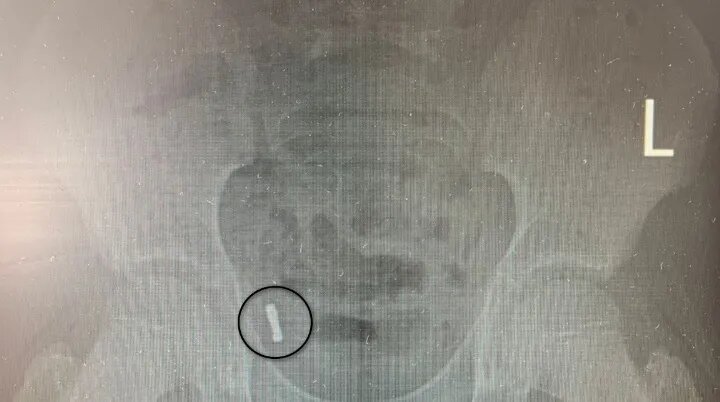

Родители ученика младших классов рассказали, что их сын проглотил магниты накануне дня обращения в больницу. Врачи оперативно сделали снимок, инородные тела обнаружили в правой подвздошной области, внизу живота. Для более тщательного анализа ситуации было решено провести наблюдение.

«Снимки на вторые и третьи сутки после обращения показали, что инородные тела не двигаются по ЖКТ, находятся без динамики в правой подвздошной области, вероятнее всего в аппендиксе», - рассказал врач ОКДБ №2 Олег Николаев.